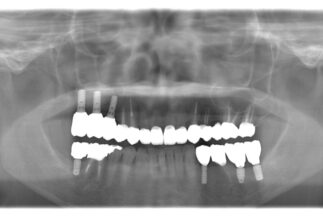

- After

【症例ステータス】

| 年齢 | 性別 | 治療期間 | 治療費概算 |

|---|---|---|---|

| 57歳 | 女性 | 2年 |

480万 ※費用は範囲によって異なります。 |

| 主訴 | |

|---|---|

| 治療内容 | 上顎右側サイナスリフト インプラント埋入上顎3本 下顎3本 上部構造モノリシックジルコニアクラウン修復 |

| リスクについて | インプラント周囲炎 スクリューの緩みなど |